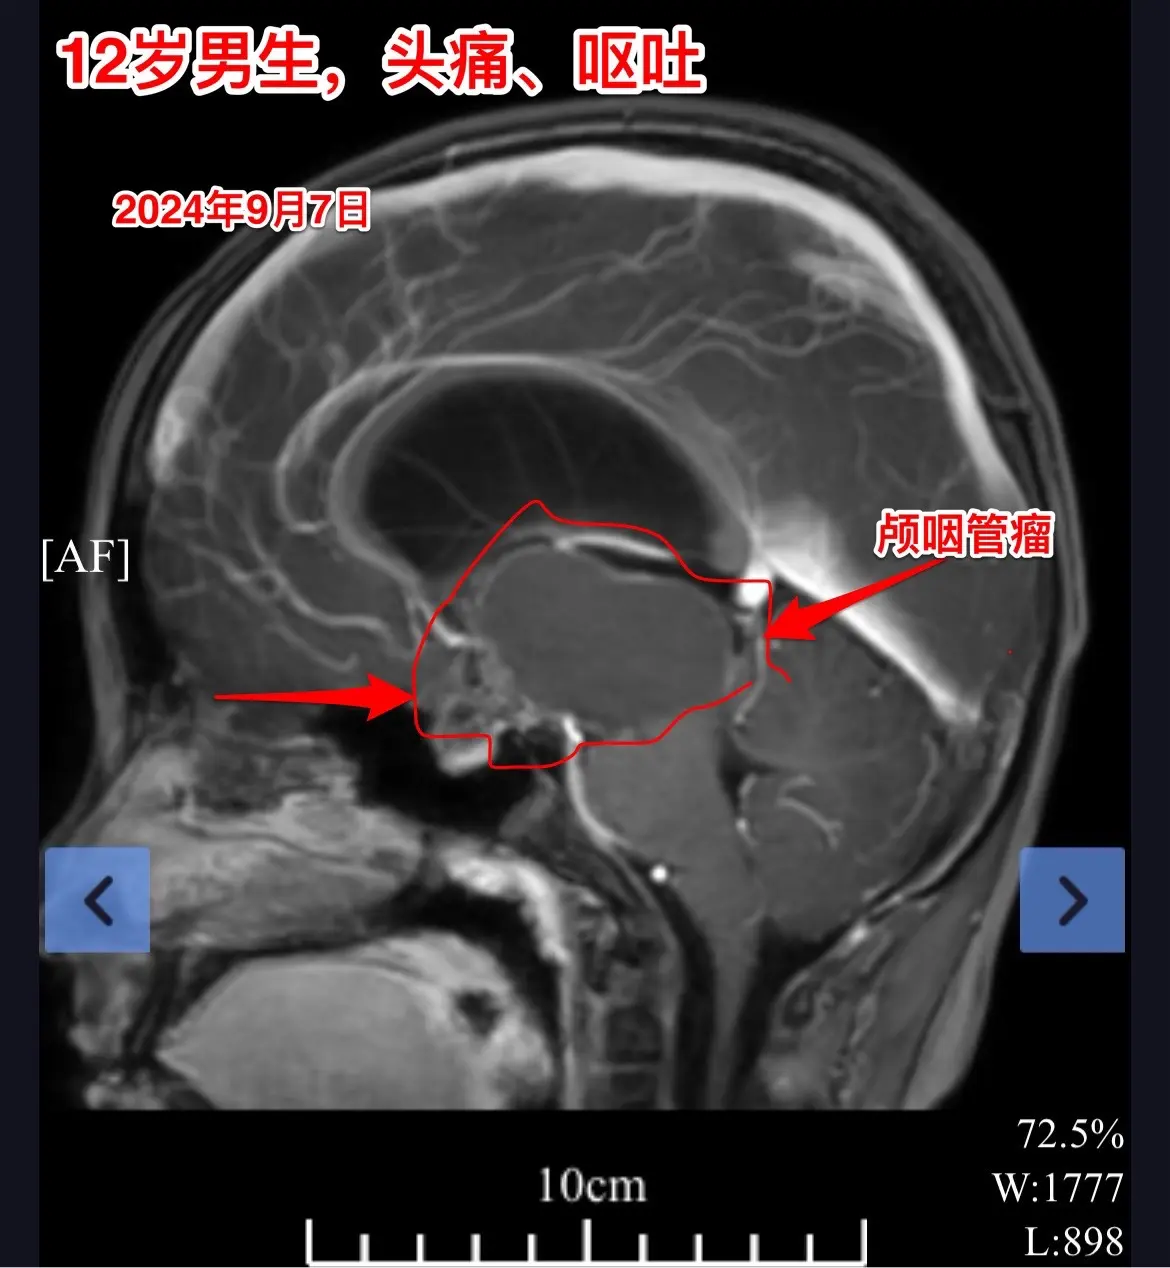

12岁南京男孩子头痛、呕吐。平时感觉身体很好,9月7日因头痛、呕吐到医院检查发现脑部长了颅咽管瘤,并且有脑积水。 9月9日到我院住院。住院时头痛、呕吐症状减轻了。复查磁共振显示颅咽管瘤的形态稍有变化,脑积水似乎有减轻。测视力发现他的视力有下降。这个颅咽管瘤生长的时间预计有两年时间,患儿症状不严重,最终因脑积水出现头痛、呕吐症状才发病。仔细检查还是可以发现一些蛛丝马迹,比如视力下降。颅咽管瘤有时会自动变小,很可能是肿瘤囊破裂了。囊变小了,脑积水就减轻了,头痛、呕吐症状就减轻了。 9月19日行开颅手术,将颅咽管瘤完全切除。手术后患者感觉视力有好转。希望肿瘤永不复发。